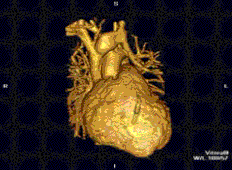

Cardiovascular

Cardiac MRI is complementary to other imaging techniques, such as echocardiography, cardiac CT, and nuclear medicine. It can be used to assess the structure and the function of the heart.[42] Its applications include assessment of myocardial ischemia and viability, cardiomyopathies, myocarditis, iron overload, vascular diseases, and congenital heart disease.[43]